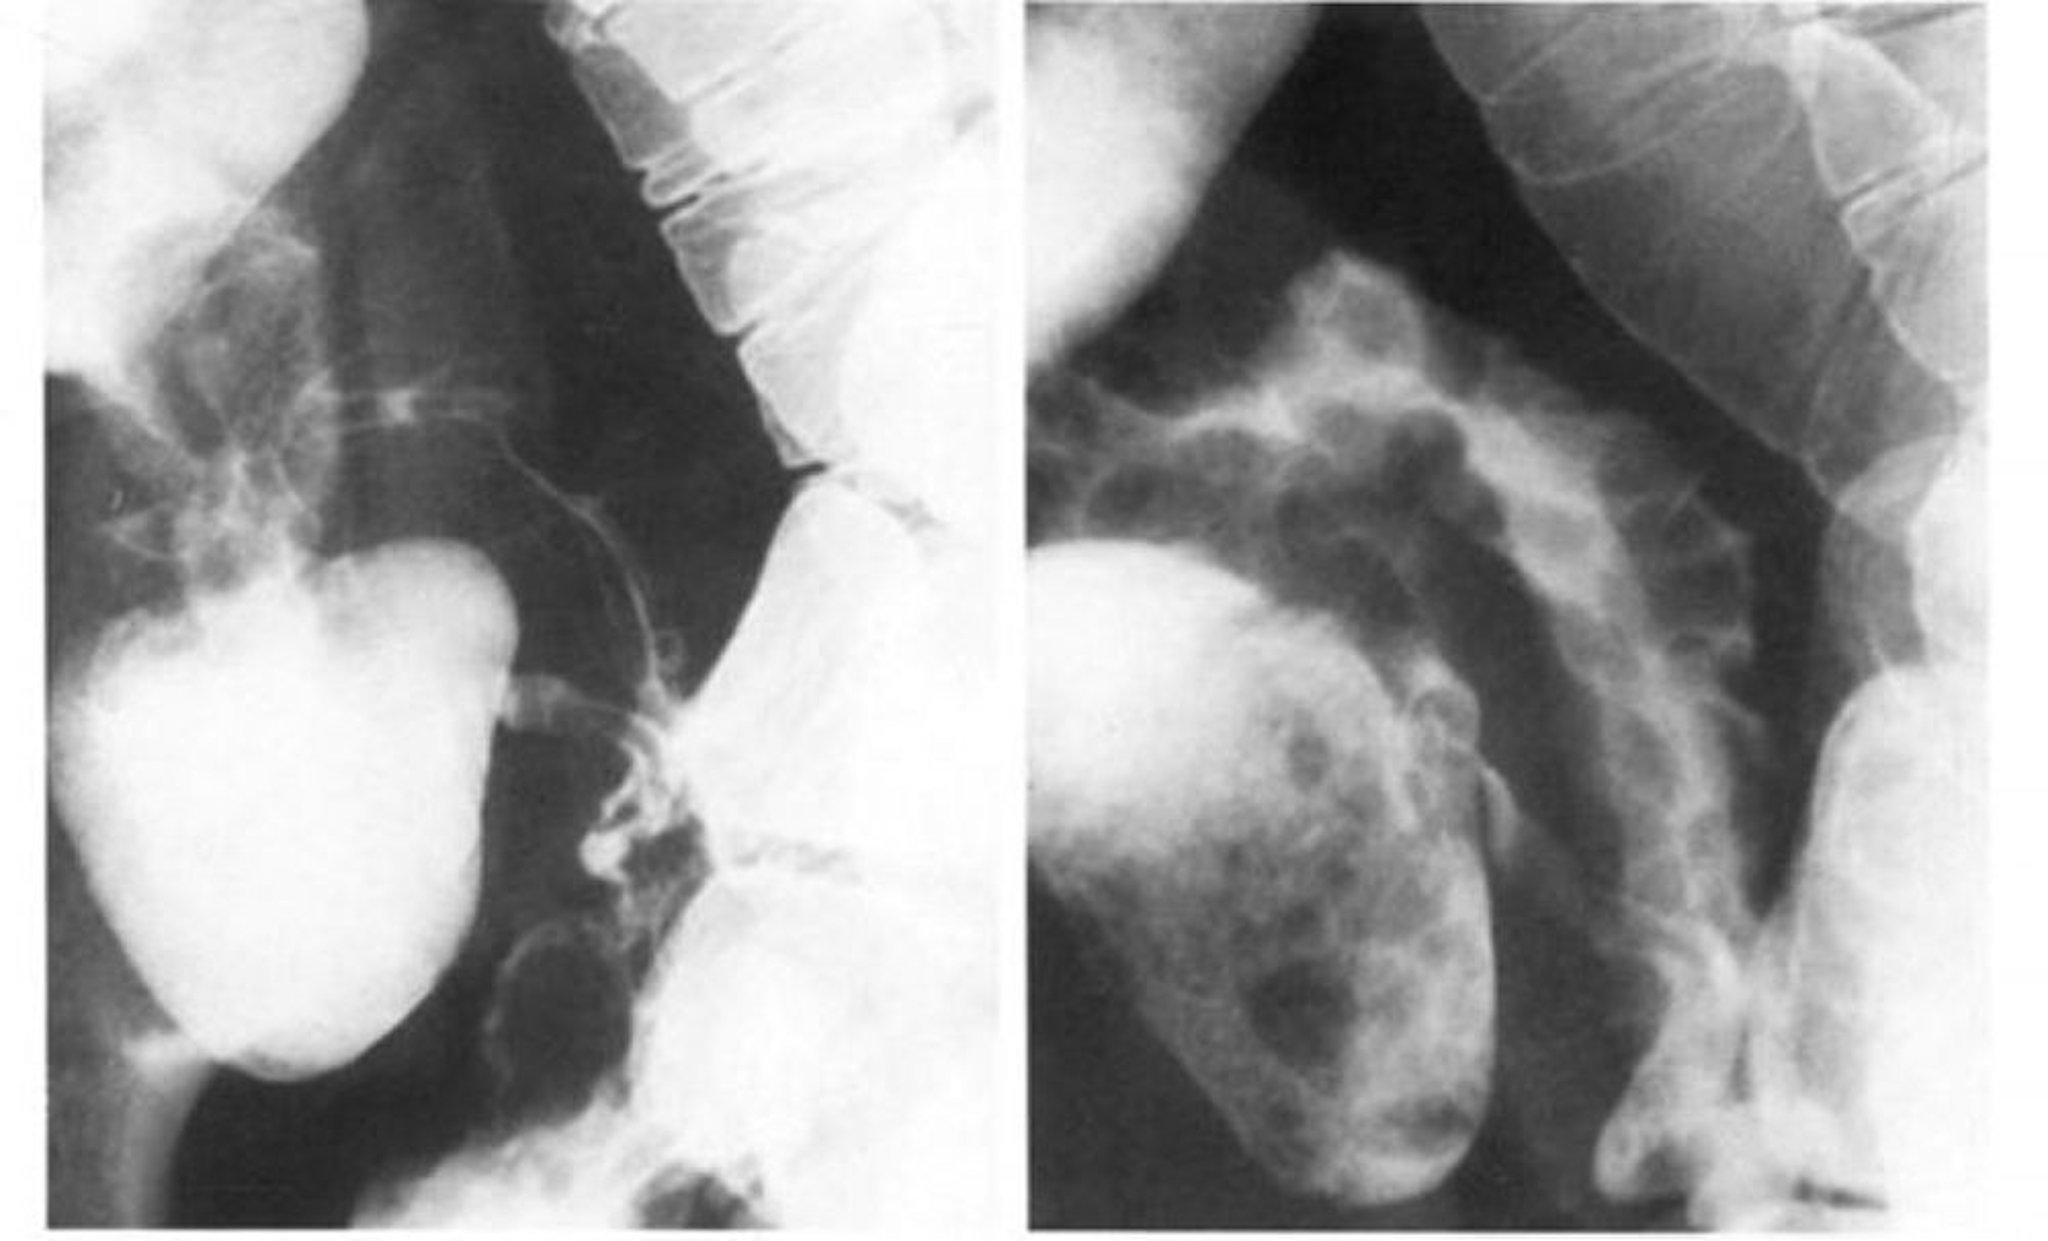

Рентгеноскопія тонкого кишечника з контрастуванням при хворобі Крона демонструє симптом струни

The left image shows the spasm obliterates the cobblestone pattern of the terminal ileum, which is best seen in double contrast in the right image.